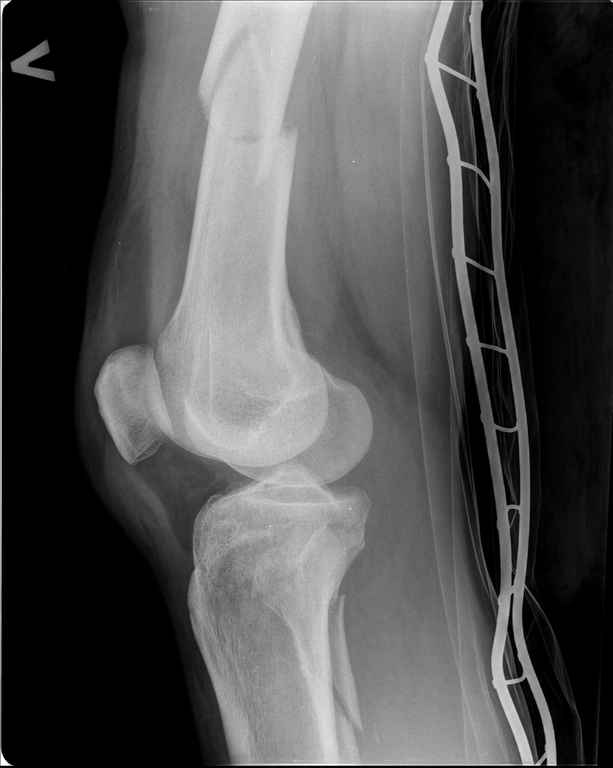

Ds: ТСТ. ЗЧМТ. СГМ. ЗТГК. О/фрагментарный перелом левого бедра. З/оскольчатый перелом с\3 левого плеча. Перелом левого локтевого отростка. З/перелом наружного мыщелка б/берцовой кости в/3 м/берцовой кости левой голени. при поступлении, ПХО раны левого бедра( рана 1х1см по наружной поверхности бедра в с/3) налажено скелетное вытяжение , и гипсовая лонгета на левую в/конечность. Находился в реанимации. 17.02.11 был прооперирован: БИОС левого плеча, о/синтез левого локтевого отростка по Веберу, БИОС левого бедра (длинная версия Fi-Can Sanatmetal диаметр 10мм), мыщелок голени трогать не стали.при остеосинтезе бедра возникли трудности при закрытй репозиции перелома в н/3, в связи с чем решили открыться внизу , отрепонировали без особого труда и выполнили блокирование во фронтальной плоскости 3-мя винтами + 1 винт спереди гвоздя (промазал). Убрал костодержатель, все нормально, контроль ЭОПом стояние отломков нормальное, зашились. На контрольной R-мме на утро выявлено вторичное смещение дистального отломка. Левая нога по сравнению со здоровой удлиннена до 2,5см( это за счет вальгусной установки гвоздя в проксимальном отделе, боялся свалиться на варус). Теперь думаем как поправить положение отломков в н/3, и зафиксировать так чтобы не съехало. Наше предложение расшиться в н/3 бедра, разблокироваться, перелом отрепонировать вновь и установить 1или 2отклоняющих винта в сагитальной плоскости, затем заблокироваться во фронтальной плоскости снова. Помогите советом, как выйти достойно из сложившейся ситуации. Заранее спасибо.

А еще может в латеральный мыщелок 2 канюлированных винта и - "ранняя функция, поздняя нагрузка". Случай непростой, удачи.